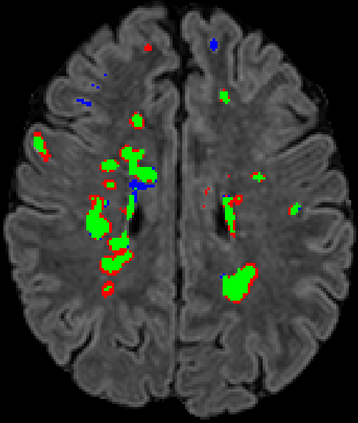

Recently, segmentation methods based on Convolutional Neural Networks (CNNs) showed promising performance in automatic Multiple Sclerosis (MS) lesions segmentation. These techniques have even outperformed human experts in controlled evaluation conditions such as Longitudinal MS Lesion Segmentation Challenge (ISBI Challenge). However state-of-the-art approaches trained to perform well on highly-controlled datasets fail to generalize on clinical data from unseen datasets. Instead of proposing another improvement of the segmentation accuracy, we propose a novel method robust to domain shift and performing well on unseen datasets, called DeepLesionBrain (DLB). This generalization property results from three main contributions. First, DLB is based on a large group of compact 3D CNNs. This spatially distributed strategy ensures a robust prediction despite the risk of generalization failure of some individual networks. Second, DLB includes a new image quality data augmentation to reduce dependency to training data specificity (e.g., acquisition protocol). Finally, to learn a more generalizable representation of MS lesions, we propose a hierarchical specialization learning (HSL). HSL is performed by pre-training a generic network over the whole brain, before using its weights as initialization to locally specialized networks. By this end, DLB learns both generic features extracted at global image level and specific features extracted at local image level. DLB generalization was validated in cross-dataset experiments on MSSEG'16, ISBI challenge, and in-house datasets. During experiments, DLB showed higher segmentation accuracy, better segmentation consistency and greater generalization performance compared to state-of-the-art methods. Therefore, DLB offers a robust framework well-suited for clinical practice.